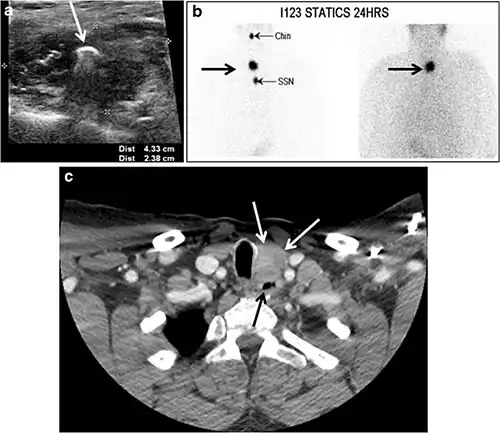

Fig. 8. A 48-year-old male patient post total thyroidectomy with PTC recurrence. a Transverse greyscale ultrasound of the neck demonstrates a left thyroid bed heterogeneous, predominantly hypoechoic irregular lesion with calcifications (white arrow). b A spot image of iodine 123 total body scan of the neck demonstrate a focus of abnormal radiotracer uptake at the left thyroid bed (Black arrows) between the annotated markers. c Enhanced axial CT scan of the neck demonstrates an enhancing large left thyroid bed mass (white arrow) with no calcifications. The lesion exerts a mass effect on the oesophagus (black arrow) and is inseparable from the trachea.[1] -

Fig. 9. A 58-year-old male patient with persistence PTC at thyroid bed with hypervascular nodal metastasis. a–c Transverse greyscale and colour Doppler neck ultrasound demonstrate hypoehoic soft tissue in the left thyroid bed (white arrow in a). There are a heterogeneous enlarged lymph nodes at level 2 and 3 with markedly increased vascularity (white arrow in b and c). d–f Enhanced axial CT images of the neck demonstrate a 2.7 × 1.4 cm hypodense soft tissue lesion anterior to the left carotid sheath (white arrow). There are left-sided enhancing abnormal and enlarged lymph nodes at cervical level 2 and 3 (black arrows).[1]